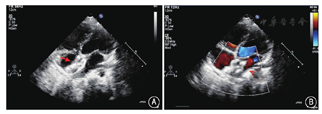

成年患者在局部麻醉下接受治疗,不能配合的患儿在镇静状态下(自主呼吸)下接受治疗,封堵治疗全程在经胸超声引导下进行,手术开始前再次通过不同超声切面及三维图像,确定目标封堵孔的位置。术前予静脉注射肝素80 U/kg抗凝。消毒、铺单后,经股静脉穿刺送入导管和导丝至右心房。在超声监视下,后撤导丝,调整导管方向和位置,将导管经预先选定的ASD送入左心房(图4)。经导管推送导丝进入左心房,退出导管。沿导丝将输送鞘管送入左心房,退出导丝。在超声监视下,经输送鞘推送根据3D打印模型选定的封堵器进行封堵(图5)。封堵器置入后,超声评估封堵器位置和形态、封堵效果,确认封堵器对二尖瓣、肺静脉及冠状静脉窦等周围结构无影响后,释放封堵器,退出输送鞘管,穿刺点压迫止血,绷带加压包扎。如果封堵后残余分流>5 mm,在增加封堵器尺寸或个数后仍不能成功封堵缺损,则患者改常规外科手术。